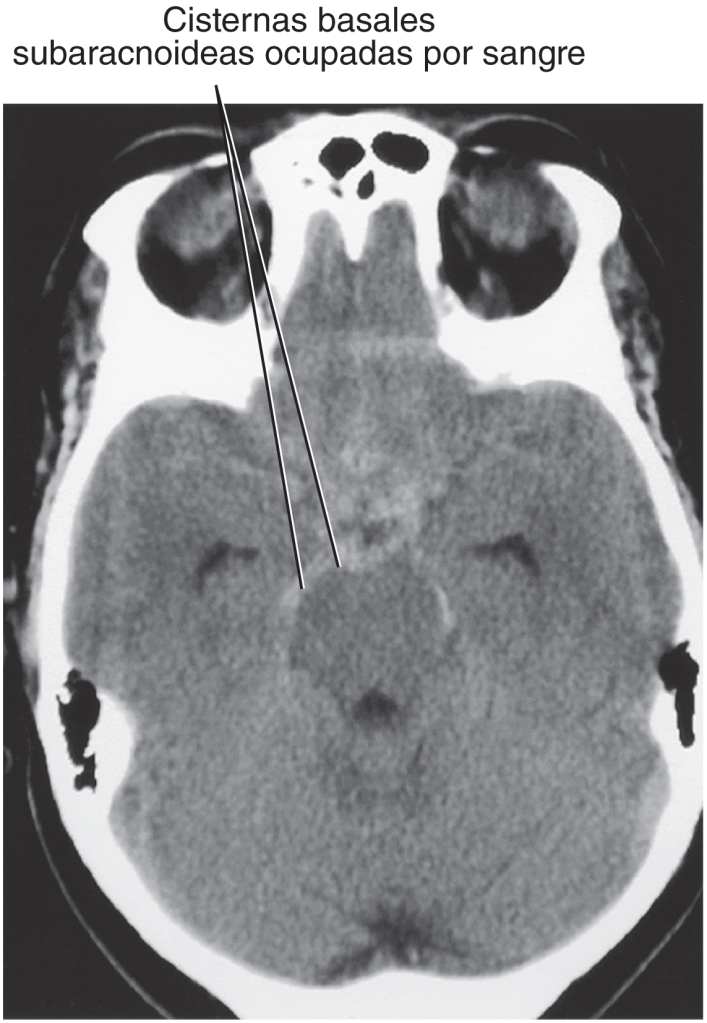

Imagen: Hemorragia subaracnoidea. Las hemorragias subaracnoideas pueden presentarse en pacientes que han sufrido traumatismos cerebrales de consideración, aunque normalmente se producen por la rotura de un aneurisma intracerebral que afecta a vasos relacionados con el círculo arterial (polígono de Willis). Descripción: Hemorragia subaracnoidea. Tomografía computarizada axial del encéfalo. 127 La tomografía computarizada del cerebro muestra cisternas subaracnoideas basales marcadas con una etiqueta que dice ‘Cisternas basales subaracnoideas ocupadas por sangre’. Fuente: Gray. Anatomía básica. Drake, Richard L., PhD, FAAA; Vogl, A. Wayne, PhD, FAAA; Mitchell, Adam W.M., MBBS, FRCS, FRCR; Tibbitts, Richard; Horn, Ansell© 2023.